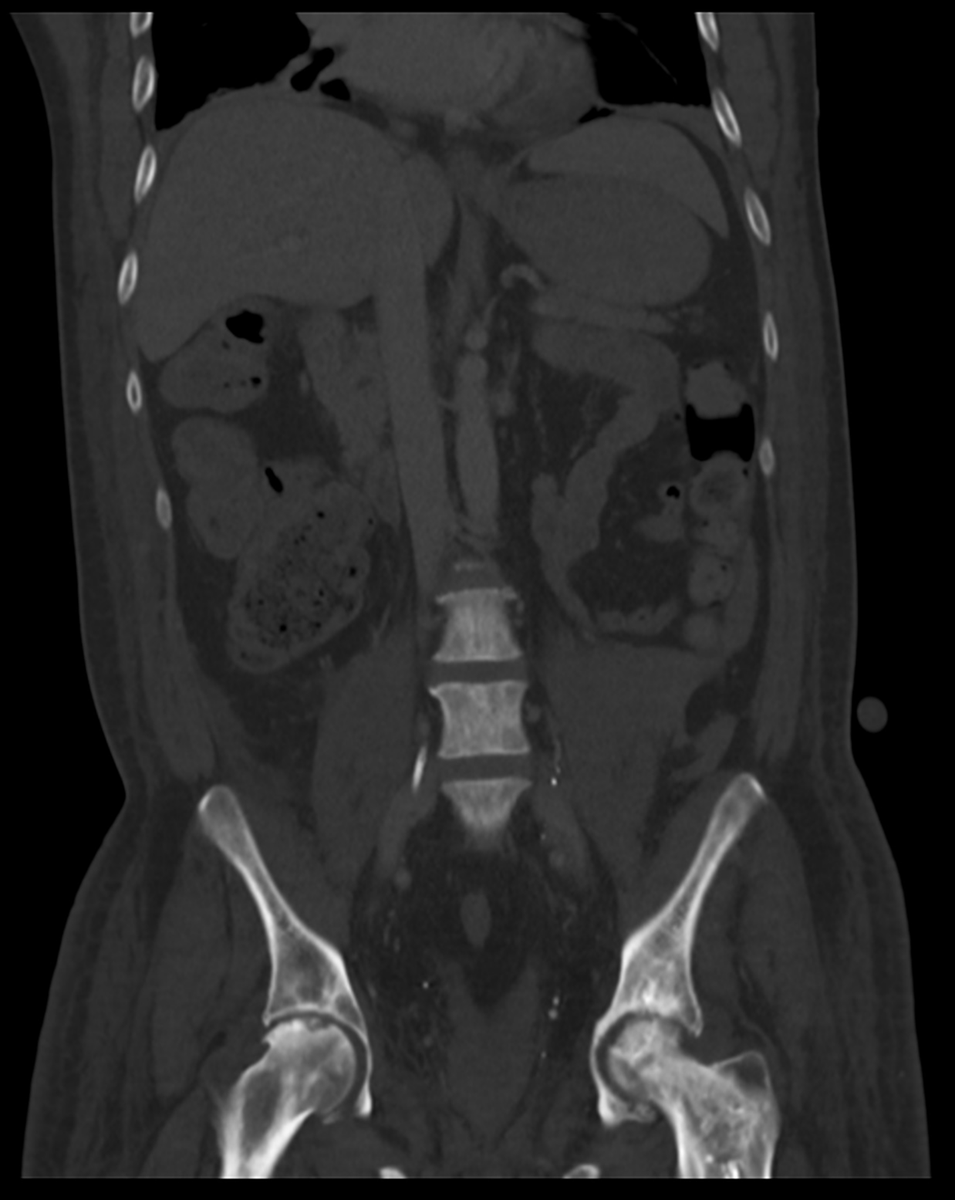

Scroll through the images in this quiz case on @Radiopaedia: radiopaedia.org/cases/d7151fa3… How many hernias can you see? I'll share the answer over the weekend! #FOAMrad